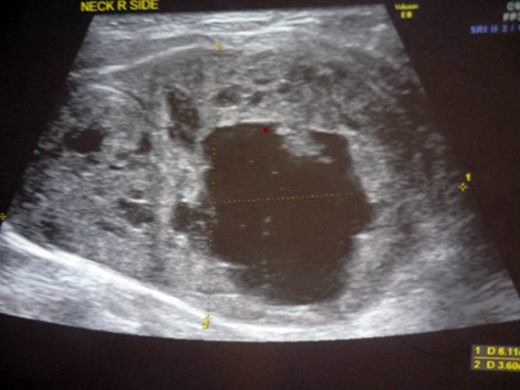

A 47-year-old male presented with a 6-month history of a progressive swelling in the right lobe of thyroid. He was euthyroid and asymptomatic. Sonography (Fig. 1) was suggestive of a right hypoechoic thyroid nodule along with a hyperechoic solid lesion adjacent to the postero-lateral aspect of the right lobe with cystic degeneration.

USG of the neck: hyperechoic cystic lesion abutting the postero-lateral aspect of the right lobe of thyroid.